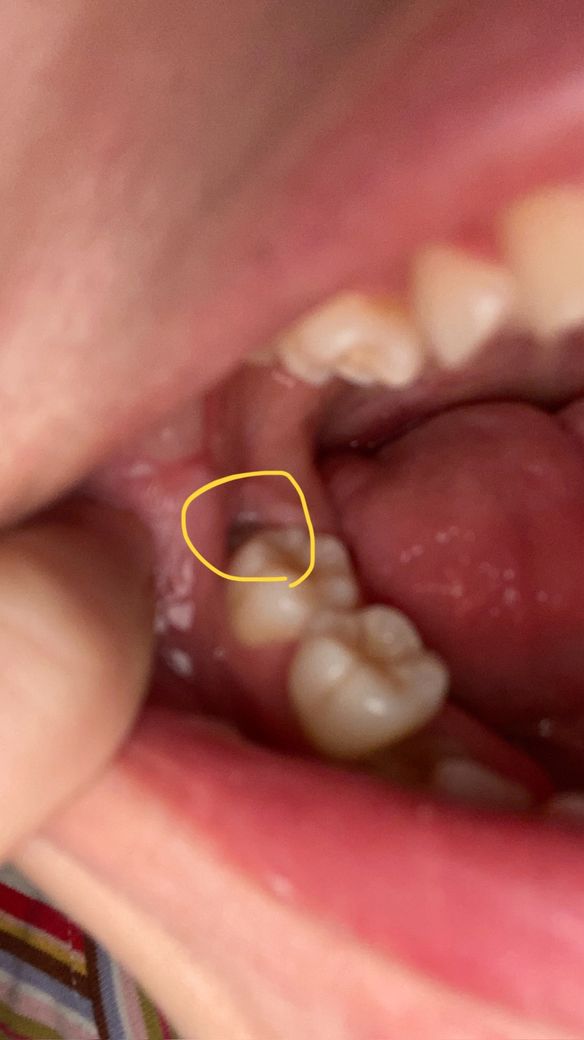

매복사랑니가 잇몸 사이로 살짝 드러나있습니다. 통증은 없는데 이런 경우는 그냥 지내도 괜찮나요?

매복 사랑니가 있는 부위인데 오늘 잇몸이 약간 들린채 사랑니가 살짝 드러나 있는 것을 발견했습니다. 너무 안쪽에 있는지라 잘 보이진않지만 색이 완전한 하얀색은 아닌거같더라고요..그런데 충치라고하기엔 제가 치통은 전혀 없어서..어제 식사 중 실수로 입벽을 깨무는 바람에 피가 많이 났었는데 그 피가 흐른것일수도 있을까요? 아직까지 사랑니로 인한 치통은 느껴본적이 없어 이런 경우는 어떻게 해야하는지 여쭤봅니다. 참고로 생리 전 pms 때 잇몸이 가끔가다 약해지기도합니다(항상은 아니고요). 그리고 요즘 몸이 피곤한지 구내염을 입안 곳곳에 달고살기도합니다

구멍이 있어서 그림자가 져서 어둡게 보이는 것 같고 사랑니에 충치가 있는건지는 확실하지 않습니다

앞 어금니와 근접해있으면 앞 어금니의 충치를 유발할 수 있으므로 빼는것이 좋습니다